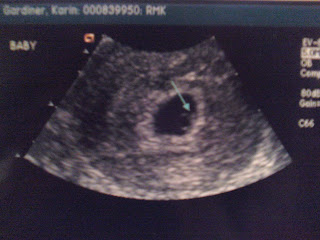

Two or three weeks ago I found out that I was pregnant. We have been trying since November so I was really excited!... And a little nervous. I was having some issues that made me even more nervous and after having my blood drawn I was told my HcG was looking good and what I was going through is completely normal. Well, my "issue" got worse and so I called the doctor again and had a blood test again (boo). My numbers had more than tripled so everything looked good, but that just didn't make sense. I was for sure she was going to tell me they went down and that I had miscarried. What a pleasant surprise, right? What a roller coaster. Well because my issue was still getting worse, she had me go to the hospital where I had an ultrasound and a trans-vaginal ultrasound (sounds fun, eh). Well to my surprise she found our little baby and we were able to see the little heart beat! I almost started crying, I could not believe it :). I was so stoked all morning, she even printed out a picture for me.